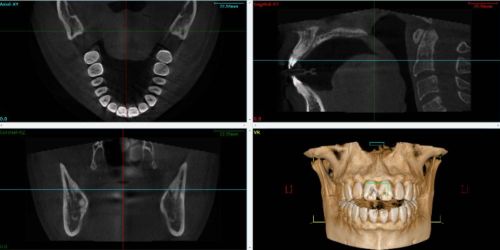

Le CBCT1 est largement utilisé en dentisterie, il est indiqué dans différentes disciplines (implantologie, orthodontie, chirurgie maxillo-faciale, diagnostic des troubles articulaires…). Le logiciel TWIM™ offre la possibilité d’intégrer cette donnée afin de construire un patient virtuel dynamique avec les données du patient.

Le Cone Beam utilise un faisceau de rayons X conique et de largeur constante. Le principe est identique à celui de la radiologie conventionnelle dont se servent les praticiens tous les jours. L’appareil effectue une rotation autour de l’objet examiné et réalise une projection sur un capteur numérique à chaque impulsion. Le cone beam permet d’obtenir directement le volume de l’objet par calcul informatique à partir des multiples projections 2D acquises durant la rotation de l’appareil. Les données de sortie sont au format DICOM2.

Pour faire une analyse des ATM3, il est recommandé de réaliser des scanners grand champ incluant l’intégralité des maxillaires. De plus, la qualité des fichiers est directement liée à la procédure de segmentation, il faut porter une attention sur l’intégrité des données au niveau des structures osseuses de l’ATM.